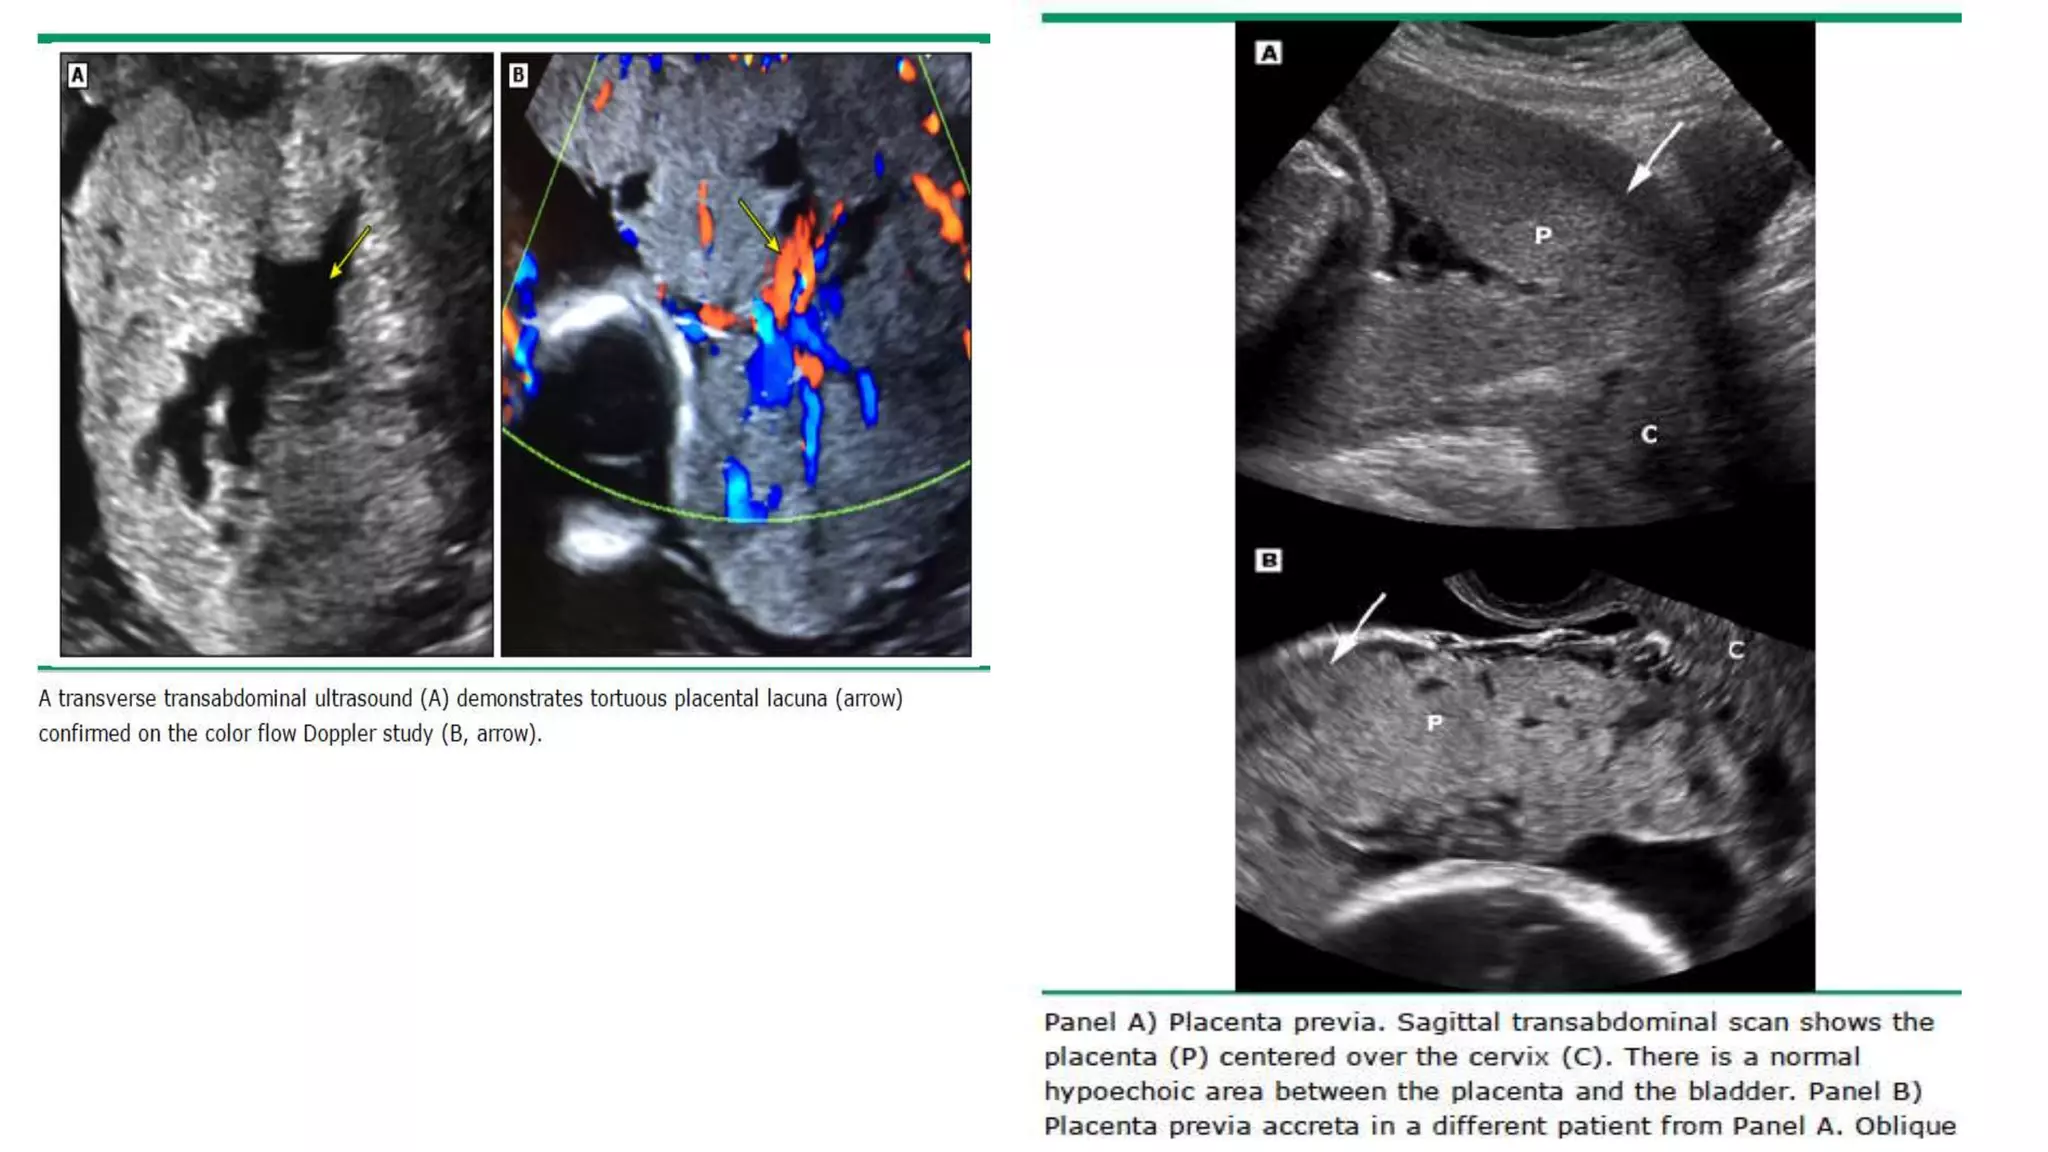

2nd and 3rd trimesters US findings suggestive of placenta

accreta

• Loss of placental homogeneity, which is replaced by multiple

intraplacental sonolucent spaces (venous lakes or placental lacunae)

adjacent to the involved myometrium. This is the most consistent

ultrasound finding.

• Loss or thinning of the normal hypoechoic area behind the placenta

(termed the ‘clear space’).

• Retroplacental myometrial thickness of <1 mm.

• Loss or disruption of the normally continuous white line representing

the bladder wall uterine serosa interface (termed the ‘bladder line’),

bulging of the placenta into the posterior wall of the bladder.

Color Doppler

• Used in conjunction with the other ultrasound findings.

• Abnormal vasculature on color Doppler ultrasound has the best

combination of sensitivity and specificity for prediction of invasive

placentation.

• Specific findings suggestive of placenta accreta include :

• Diffuse or focal intraparenchymal lacunar flow

• ● Vascular lakes with turbulent flow “chaotic”

• ● Hypervascularity of serosa-bladder interface

• ● Prominent sub-placental venous complex.